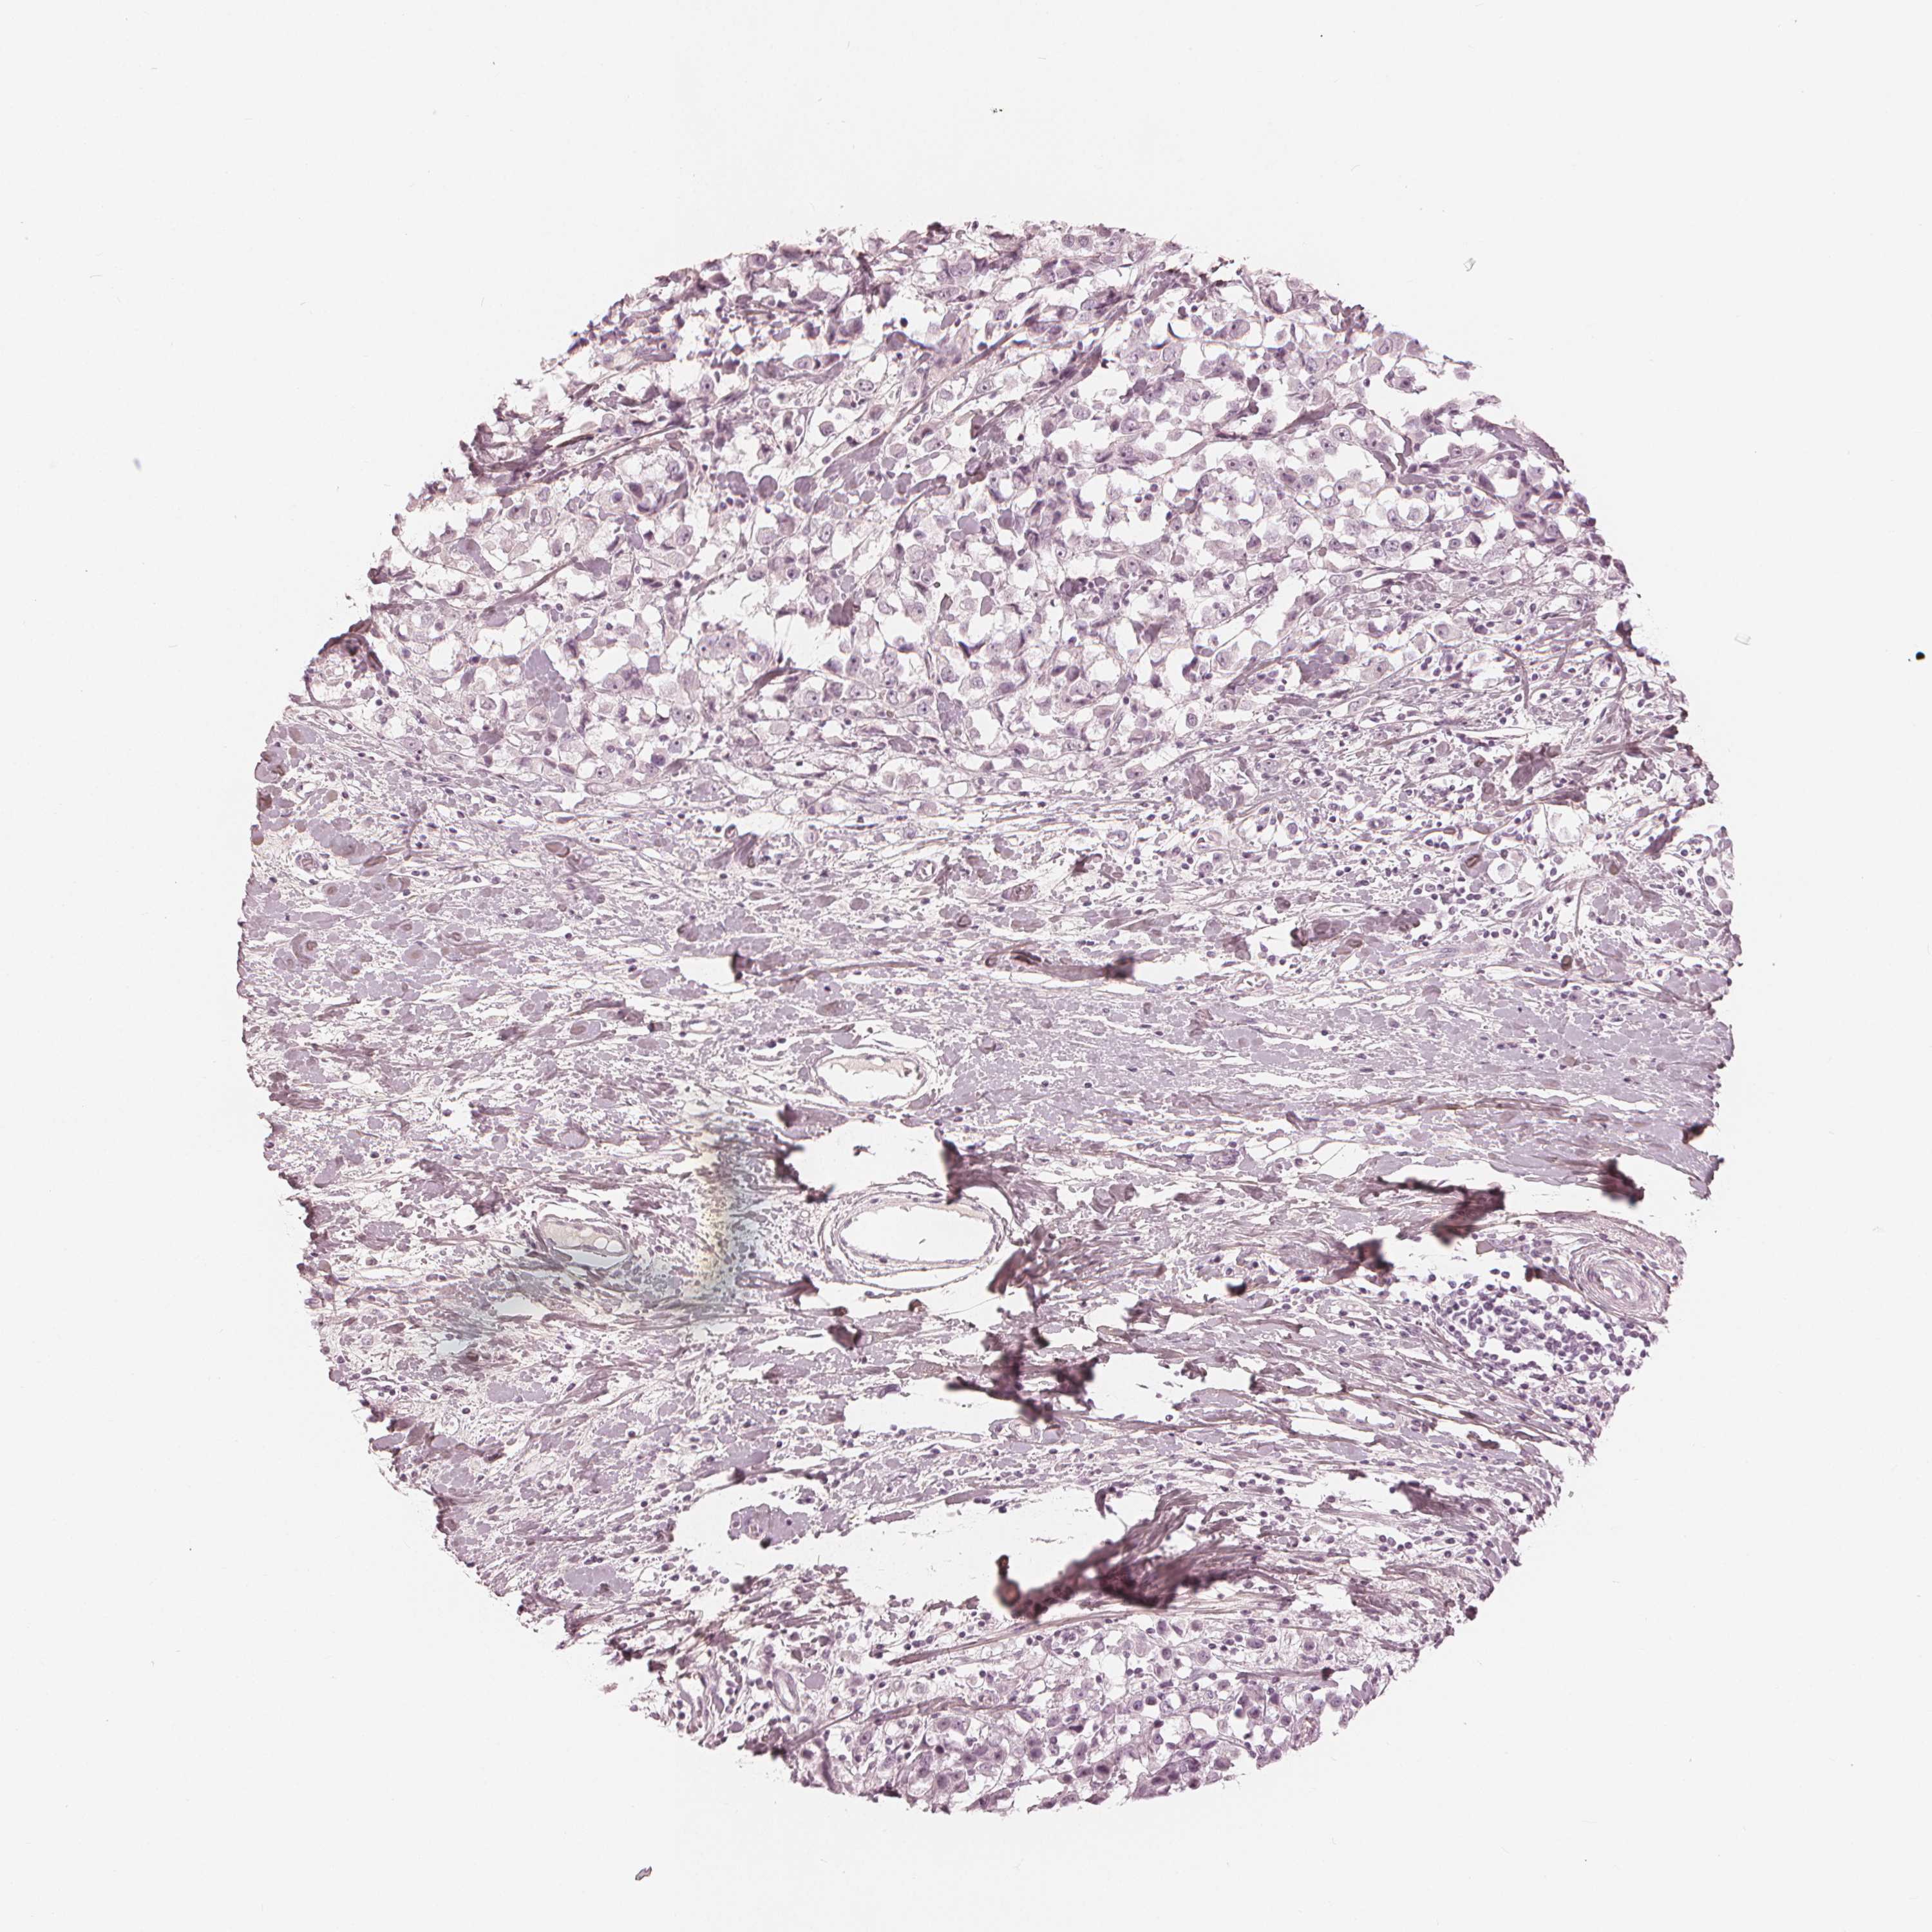

CANCER BREAST CANCER Show tissue menu

Breast cancer

Human cancer